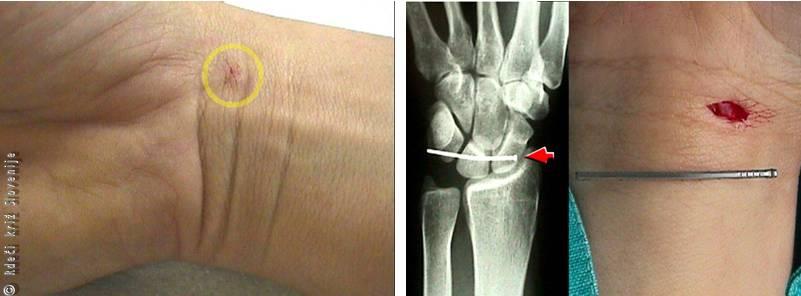

Primer 1

36-letna bolnica se je s konico ozkega noža v službi zabodla na dlančno stran podlakti leve roke. Nad zapestjem je bila pol centimetra velika vstopna rana iz katere je tekla modrikasta kri (venska krvavitev). Področje zapestja je bilo oteklo in boleče. Pri pregledu ni imela motenj občutljivosti in roka je bila topla, normalno prekrvljena, pulz arterije (ulnaris) na mezinčevi strani je bil dobro tipen, pulz arterije (radialis) na palčevi strani pa je bil slabše tipen. Gibljivost zapestja in prstov je bila ohranjena.

Slika 6

Pri vbodnih ranah moramo pomisliti tudi na tujke, ki ostanejo v globlje ležečih tkivih in povzročajo bolečine. Pletilna igla na dlančni strani zapestja je povzročala hude bolečine pri premikanju roke, zaradi neznatne vstopne rane pa je bil izvor bolečine dlje časa neodkrit.

Pri kirurški oskrbi rane smo ugotovili prekinjene kožne vene in vejo arterije (radialis), večjo kolekcijo krvi (hematom), ki je delno stiskala radialno arterijo, delno prekinjeno mišico upogibalko zapestja in prstov (v kitno-mišičnem delu) in poškodovano ovojnico medianega živca.

Slika 7

Vbodna rana s konico noža. A – Majhna vstopna ranica. B – Poškodba mišice, žile in živca.